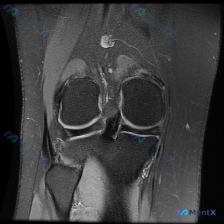

这是一张膝关节冠状位MRI图像(考虑为质子密度加权像或T2加权像,对积液和软组织病变显示更敏感),影像所见核心信息如下:

- 骨性结构:股骨远端、胫骨近端骨皮质完整,无明显骨折或骨质破坏,内外侧胫骨平台关节软骨下骨边界清晰

- 半月板:内侧半月板体部信号增高、形态不规整;外侧半月板形态完整,信号无明显异常

- 韧带:内侧副韧带、外侧副韧带结构完整,无连续性中断;后交叉韧带走行尚可,前交叉韧带因层面原因观察受限,未见异常肿块

- 其他异常:髌上囊及股骨髁间窝可见大量高信号液体影,提示大量关节腔积液;关节间隙周围及内侧软组织信号不均,考虑存在滑膜炎症或软组织水肿